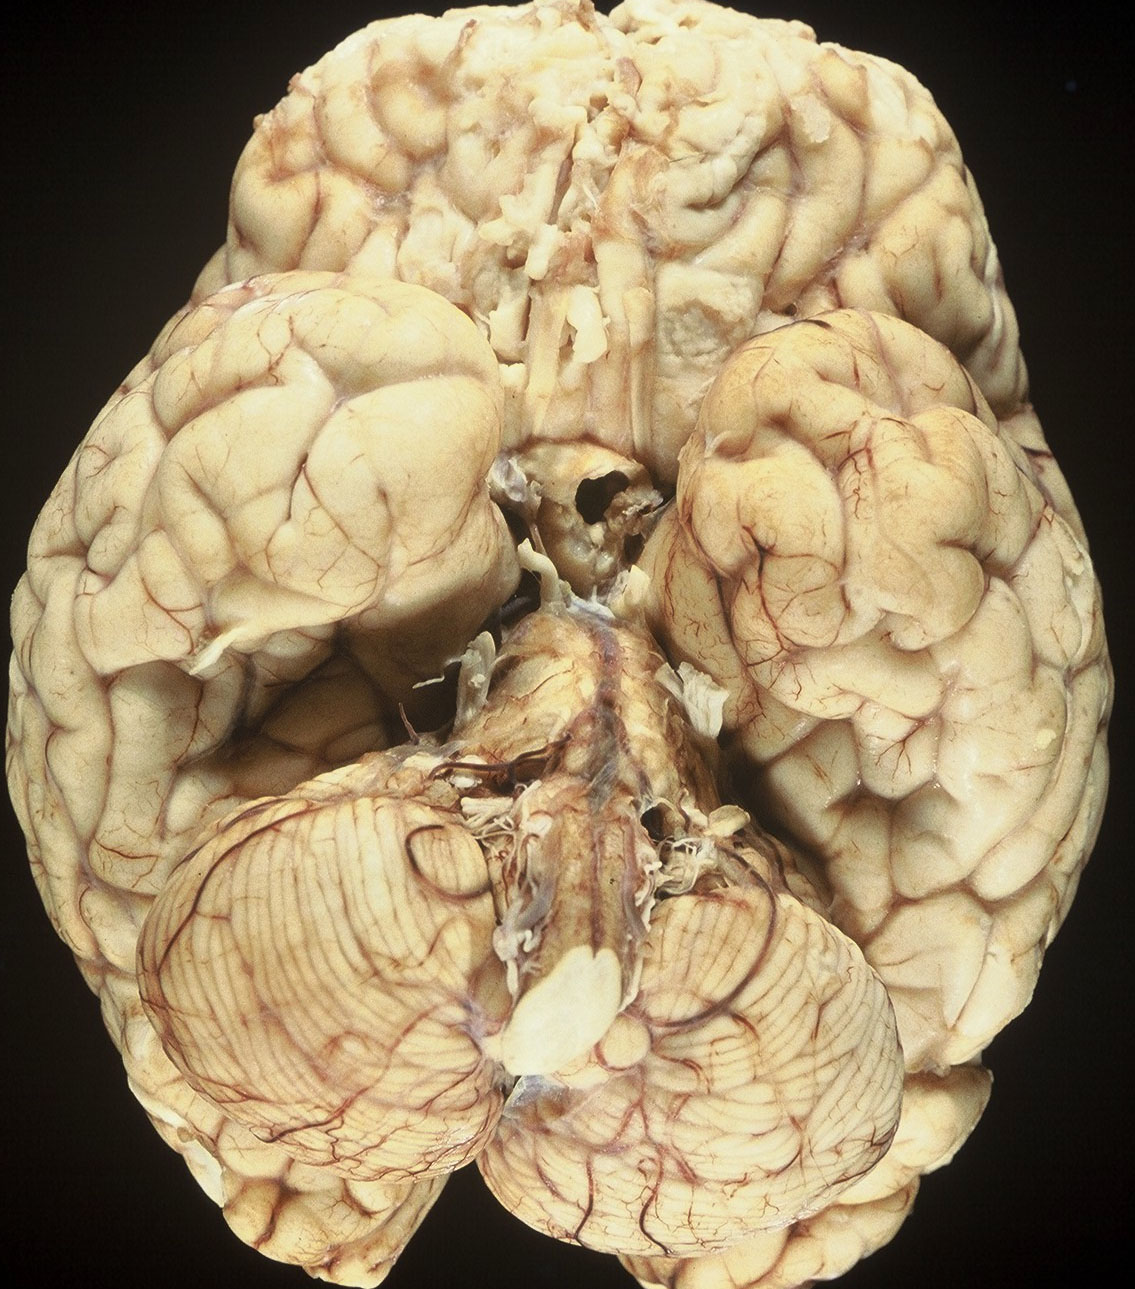

1992年の剖検所見

大脳表面,脳幹部,脊髄くも膜下腔には腫瘍が見当たりませんが,側脳室を充満するように腫瘍が増殖しています。

側脳室壁に結節状の腫瘍が無数に認められます。これは今日では,内視鏡による脳室内観察で見ることができるものです。

上方が側脳室側です。脳との境にある脳室上衣 ependyumの下に腫瘍細胞が這うように浸潤しています。そこから血管周囲 Virchow-Robin spaceを通って脳深部に浸潤しています。

大脳深部(左)と小脳深部(右)には髄質血管に沿って浸潤します。これは髄芽腫などと同様の脳浸潤所見です。